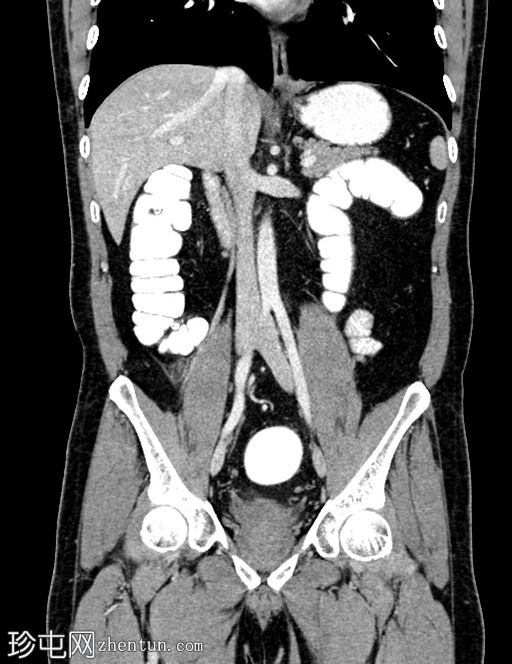

矢状位增强扫描

门静脉期

冠状位增强扫描

门静脉期,可见一持续存在的脂肪密度影,周围环绕高密度环;周围脂肪条索状改变,无脓肿形成,邻近结肠无憩室,盲肠壁正常。无阑尾炎,无淋巴结肿大,无游离气体或液体。